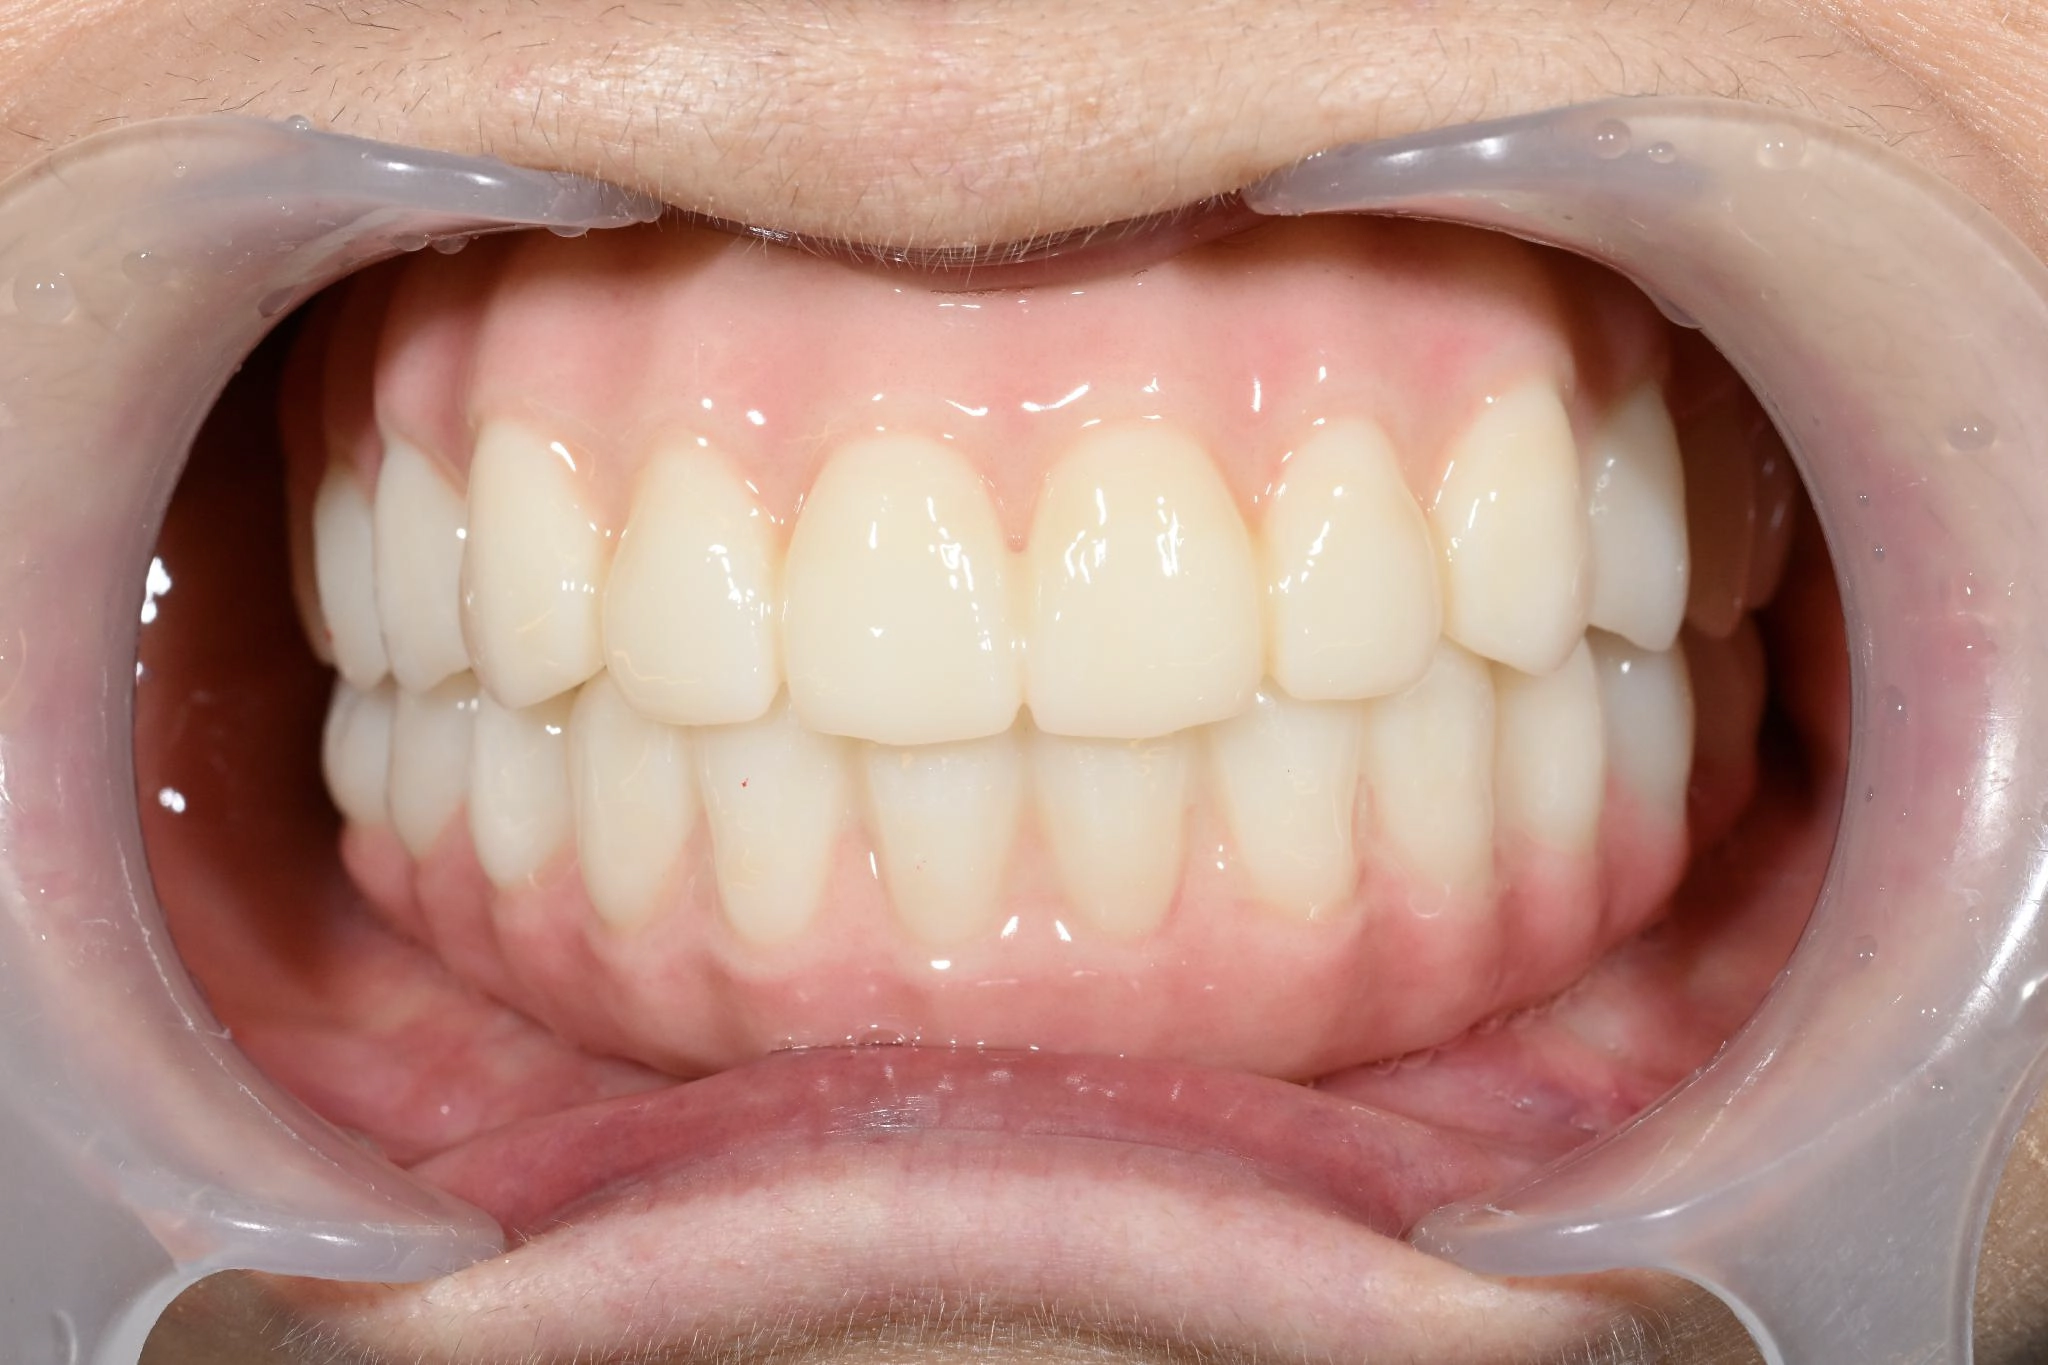

術後

内容 :上下顎オールオン4ザイゴマ2